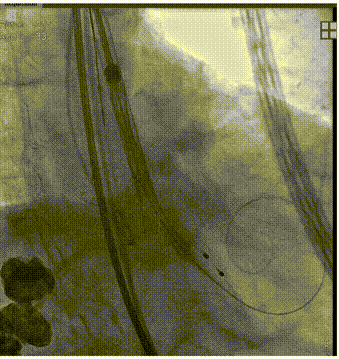

球囊预扩

输送器过弓

输送器定位

瓣膜定位

瓣膜脱钩

全息剪影

术后即刻超声评估

术后超声心动图提示:主动脉瓣人工瓣膜术后压差从61mmHg降至5mmHg,前向血流速度从4.8m/s降至1.6m/s,微量反流,左室壁搏幅正常范围,手术效果良好。